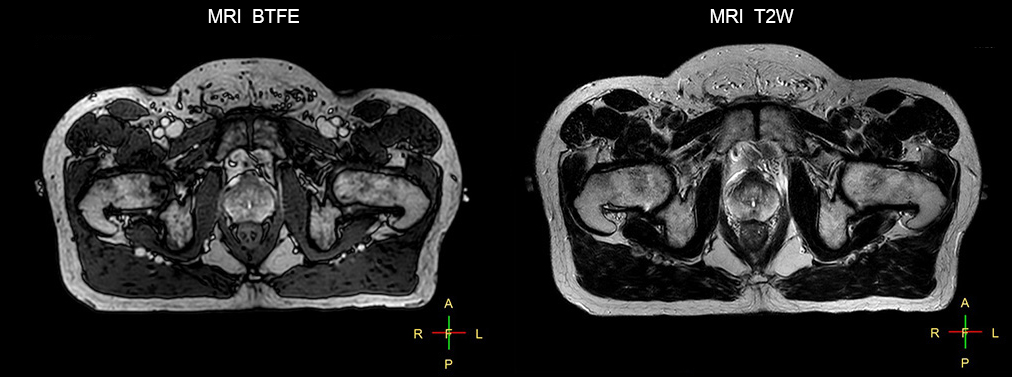

“The biggest problem for CT-based planning, especially in prostate, is you can’t see the cancer very well,” says Dr. Stevens. “On CT it can be quite challenging to see the edge of the prostate especially at the apex. When the edge of the prostate can’t be delineated well on CT, radiation oncologists will increase their margins a little bit so they don’t miss it, but that can also increase toxicity.” “Using MR, the prostate is well delineated. We quickly see the edges of cancerous tumors like in prostate cancer, and as normal structures can be defined, we can optimize the treatment plan to protect these organs and their normal function. This can potentially improve the outcome. And it improves workflow as well. We can contour more quickly, confident that the tumor is going to be in the field.” “The Ingenia 3.0T MR scanner provides high resolution allowing us to make scans fast for the patients. It also gives the potential to include methods like MR spectroscopy and diffusion weighted Imaging, which we’re in the process of doing right now,” Dr. Stevens adds.

Beaumont Health System (Royal Oak, Michigan, USA) is one of the largest health systems in the USA, with eight hospitals and 153 outpatient sites, a medical school and a research institute. The Radiation Oncology (RO) department houses a dedicated Ingenia MR-RT solution that is routinely used for clinical and research MR-RT activities. “The main reason to integrate MR imaging in RT planning is the superb soft tissue contrast that allows detailed delineation of tumors and healthy organs, which is crucial for RT planning,” says Craig W. Stevens MD, PhD. “MR also provides information on functional and biological activities in tumors, background tissue and normal organs, which may also be used in RT planning,” says physicist Di Yan, DSc, FAAPM.” “We currently use MR-RT mainly in the abdomen and pelvis region: prostate, colorectal, pancreatic, cervical, and liver. Also in the brain, we are starting to use it,” says Dr. Yan.